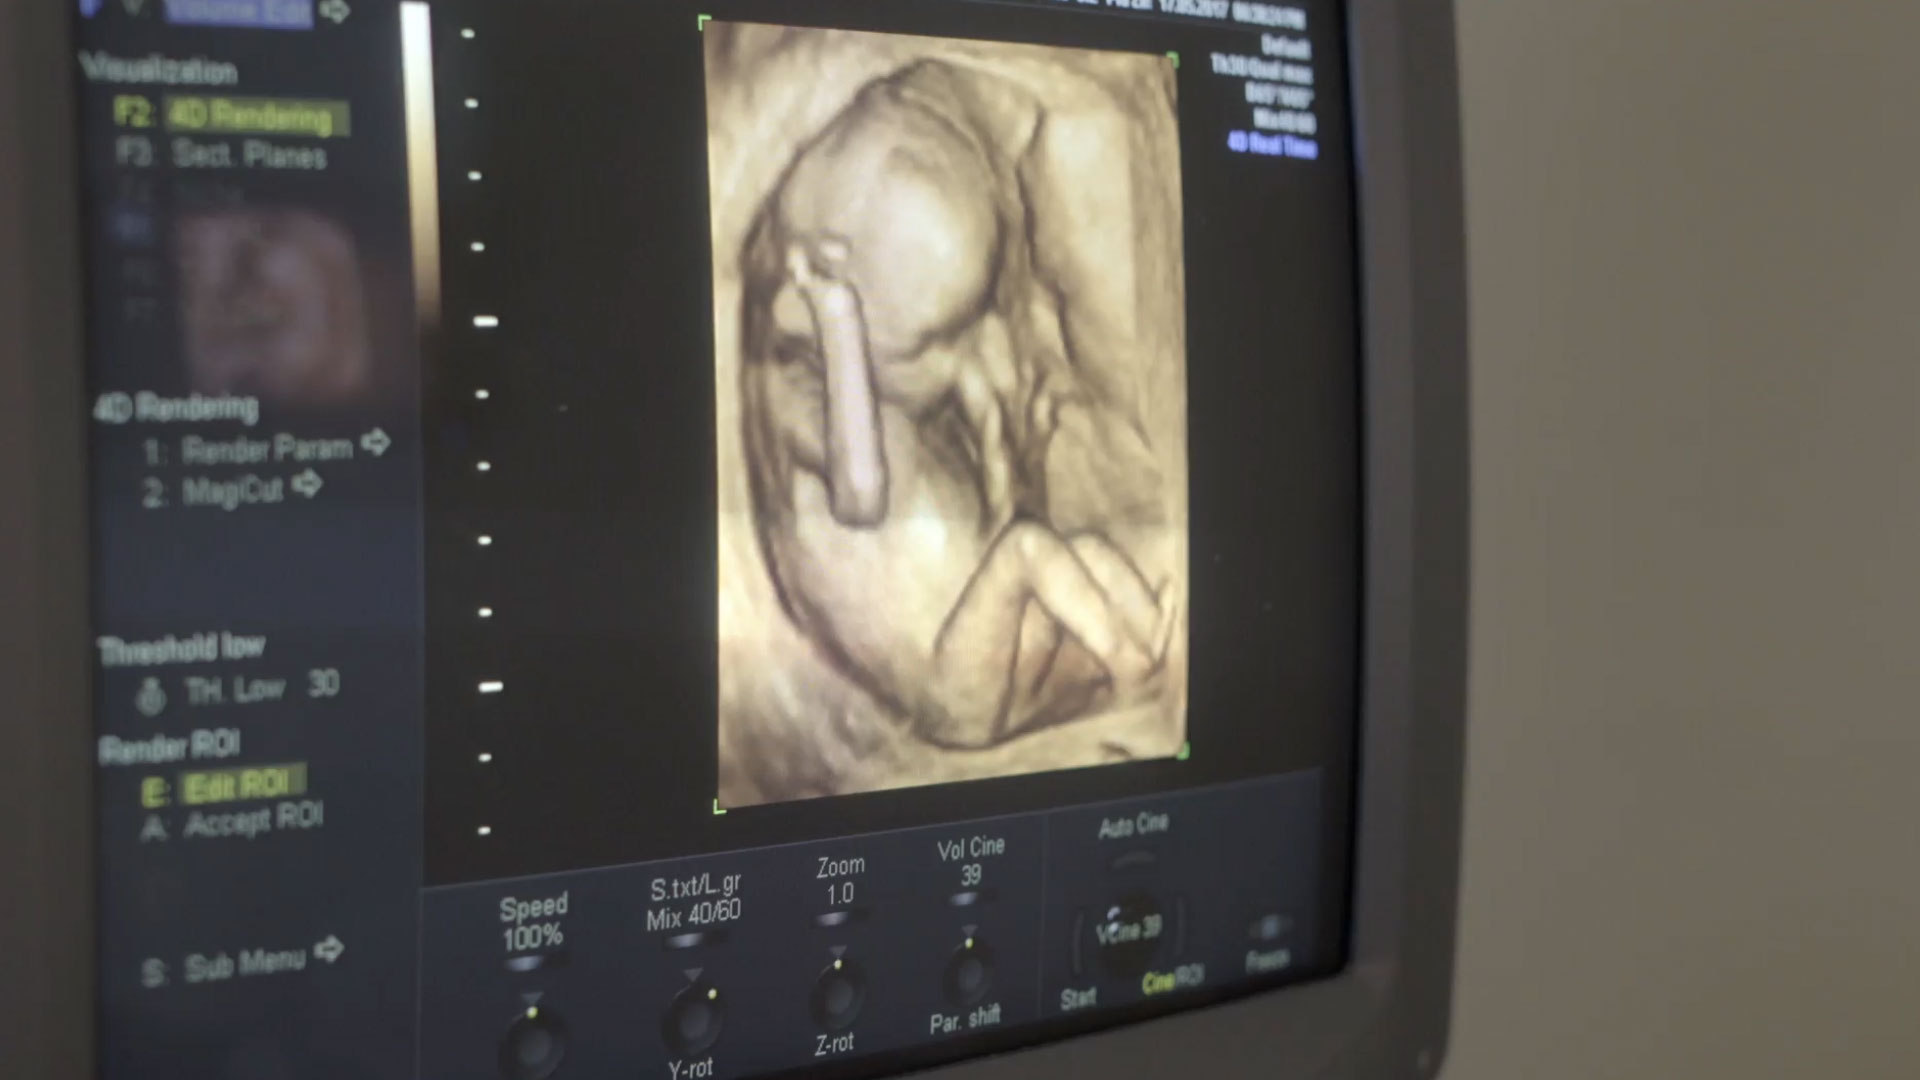

Researchers point to several factors driving the increase, including patients' ability to travel across state lines, so-called "shield laws" that allow abortions in states where the procedure is banned, and a rise in chemical abortions.

"There are no guardrails on the abortion drugs mifepristone and misoprostol. Women are ordering them online — sometimes it's coercive men. There's no verification of who is getting them," said Dr. Ingrid Skop, an OBGYN with the pro-life Charlotte Lozier Institute.

Skop told CBN News it is difficult to track the true number of chemical abortions, noting that some pills are coming from overseas.

"They're being delivered in the mail, often to pro-life states like Texas. No testing beforehand. No doctor to walk with the woman through the abortion," Skop said.